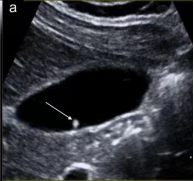

首选检查为超声检查,该检查无创、方便易行、廉价,对息肉的形态、血流有很好的判断,尤其对胆囊胆固醇沉积症、胆囊腺肌症等有独特的影像显示,是常规体检、随访的必备检查。